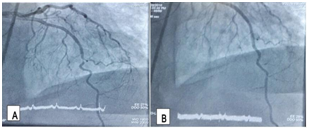

Angioplasty of the mid LAD was achieved successfully with 14'2mm .....stent. the VSR was crossed from the LV with a 6F cut pigtail and standard terumo wire 0.35 inch where it advanced into the pulmonary artery. A manually modified 6F multipurpose catheter was introduce through the internal jugular vein into the pulmonary artery where the terumo wire had been snared and exteriorized. A 20mm PIMVSD device (AGA medical) was advanced into the left ventricle and under transthoracic echocardiographic and continuous hand-injection through the already cutted pigtail into the left ventricle, the Figure 2 & Figure 3.

Figure 3 Left ventricular angiography (LAO/Cranial 35/35) before (A) and after (B) transcatheter closure of ventricular septa! repture with 20mm 13l MVSD device, small residual shunt was detected.

Angioplasty of the mid LAD was achieved successfully with 14" 2mm .....stent. the VSR was crossed from the LV with a 6F cut pigtail and standard terumo wire 0.35 inch where it advanced into the pulmonary artery. A manually modified 6F multipurpose catheter was introduce through the internal jugular vein into the pulmonary artery where the terumo wire had been snared and exteriorized. A 20mm PIMVSD device (AGA medical) was advanced into the left ventricle and under transthoracic echocardiographic and continuous hand-injection through the already cutted pigtail into the left ventricle, the device deployed completely. At that time, a significant rise in the left ventricle systolic pressure was obsereved. Only after device stability was assessed by left ventricle angiography and transthoracic echocardiography, the device was released. The patient transferred to the intensive care unit and discharged three days later with a well general condition.